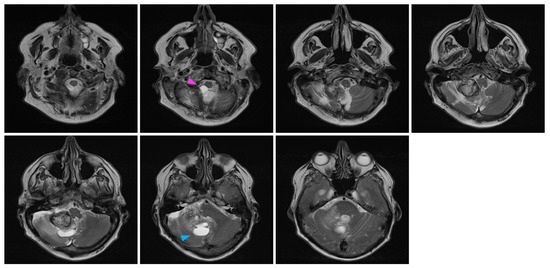

In July 2016, an MRI showed a mild increase in the lesion’s size from 24 × 17 × 17 mm to 26 × 20 × 17 mm (AP, T, CC, respectively). In the yearly imaging follow-ups, the lesion was found to be slowly shrinking, reaching a size of 18 × 13 × 14 mm in September 2020. However, at this time, the lesion still displayed a prominent cystic component that appeared to be slightly progressive. In retrospect, it appears that the solid component of the lesion remained stable while the cystic component was discreetly progressing, especially from 2018 to 2020 (Figure 2). No new lesions were found during the clinical course of the patient.

In February 2022, at the age of 72 years old, the patient was hospitalized in his hometown following the appearance of symptoms and was referred to neurosurgery. He mainly displayed loss of balance, unexplained loss of weight, confusion, and psychomotor retardation. He was able to ambulate without the aid of a walker, albeit at a very slow pace. Dexamethasone failed to improve his condition. An MRI underlined a right-sided, cerebellar intra-axial lesion located at the anterolateral portion of the cerebellar hemisphere. The lesion, determined to be a relapse of the initial HBL, displayed a nodular component in intimate proximity with the brainstem, measuring 36.2 × 32.1 × 31.9 mm (Figure 3). The presence of two cystic components were also noted. The first, located posteriorly, measured 32 mm maximally (Figure 4, blue marker). The second, located antero-infero-medially, measured 21 mm maximally and protruded in the subarachnoid space at the level of the pons (Figure 4, pink marker). The lesions caused a mass effect on the medulla, the inferior aspect of the pons, the middle cerebellar peduncle, and at the level of the 4th ventricle with associated hydrocephalus.

Figure 2. Longitudinal follow-up. Representative capture of sagittal T1-weighted MRI control imaging. The date of imaging is represented. Images are organized left to right and represent a left–right progression in the sagittal plane. The red marker highlights the appearance of an enlarging cystic component in the posterior aspect of the lesion in 2020.

Figure 4. Pre-surgical MRI of the lesion. Representative capture of the T2-weighted MRI pre-surgical imaging highlighting the two cystic components of the lesion. Coronal images are organized left to right and represent a posterior-to-anterior progression in the coronal plane. The pink marker highlights a 21 mm antero-infero-medial cystic lesion, while the blue marker highlights a 32 mm posterior cystic lesion.